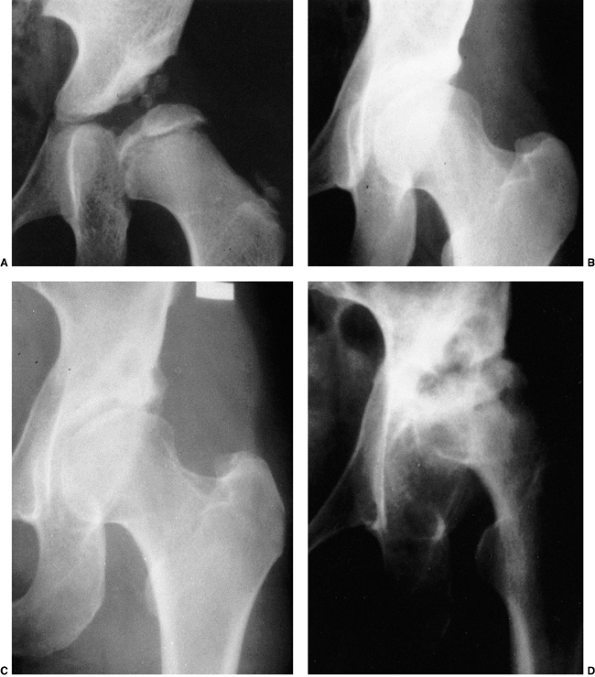

Figure 24.9 A:

An 18-month-old girl with bilateral high dislocations. Note the poorly developed acetabula with well-developed secondary acetabula. B: At 33 months of age, the irregular ossification centers in the left and right hip have coalesced, with a slight improvement in the acetabular index. C: When the girl is 7 years of age, an anteroposterior view shows the appearance of the accessory centers of ossification in the periphery of the acetabulum. D: The accessory centers of ossification are somewhat better appreciated in the abduction view at 7 years of age. E: An anteroposterior view at 8 years of age shows the coalescence of the accessory centers of ossification, increasing the depth of the acetabulum. Note the excellent sourcil formation. F: The accessory centers of ossification are well demonstrated in an abduction view at 8 years of age. |